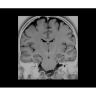

• NeuroWorks — универсальное решение для визуализации анатомии головного мозга, позвоночника, сосудов и периферических нервов с четкой дифференциацией тканей.

• 48-канальная катушка TDI для головы, входящая в базовую комплектацию SIGNA Architect, обеспечивает феноменальную производительность с учетом особенностей каждого пациента. Благодаря гибкому и универсальному дизайну, высокому соотношению сигнал/шум и передовым технологиям визуализации, таким как HyperWorks, учитываются потребности подавляющего большинства пациентов.